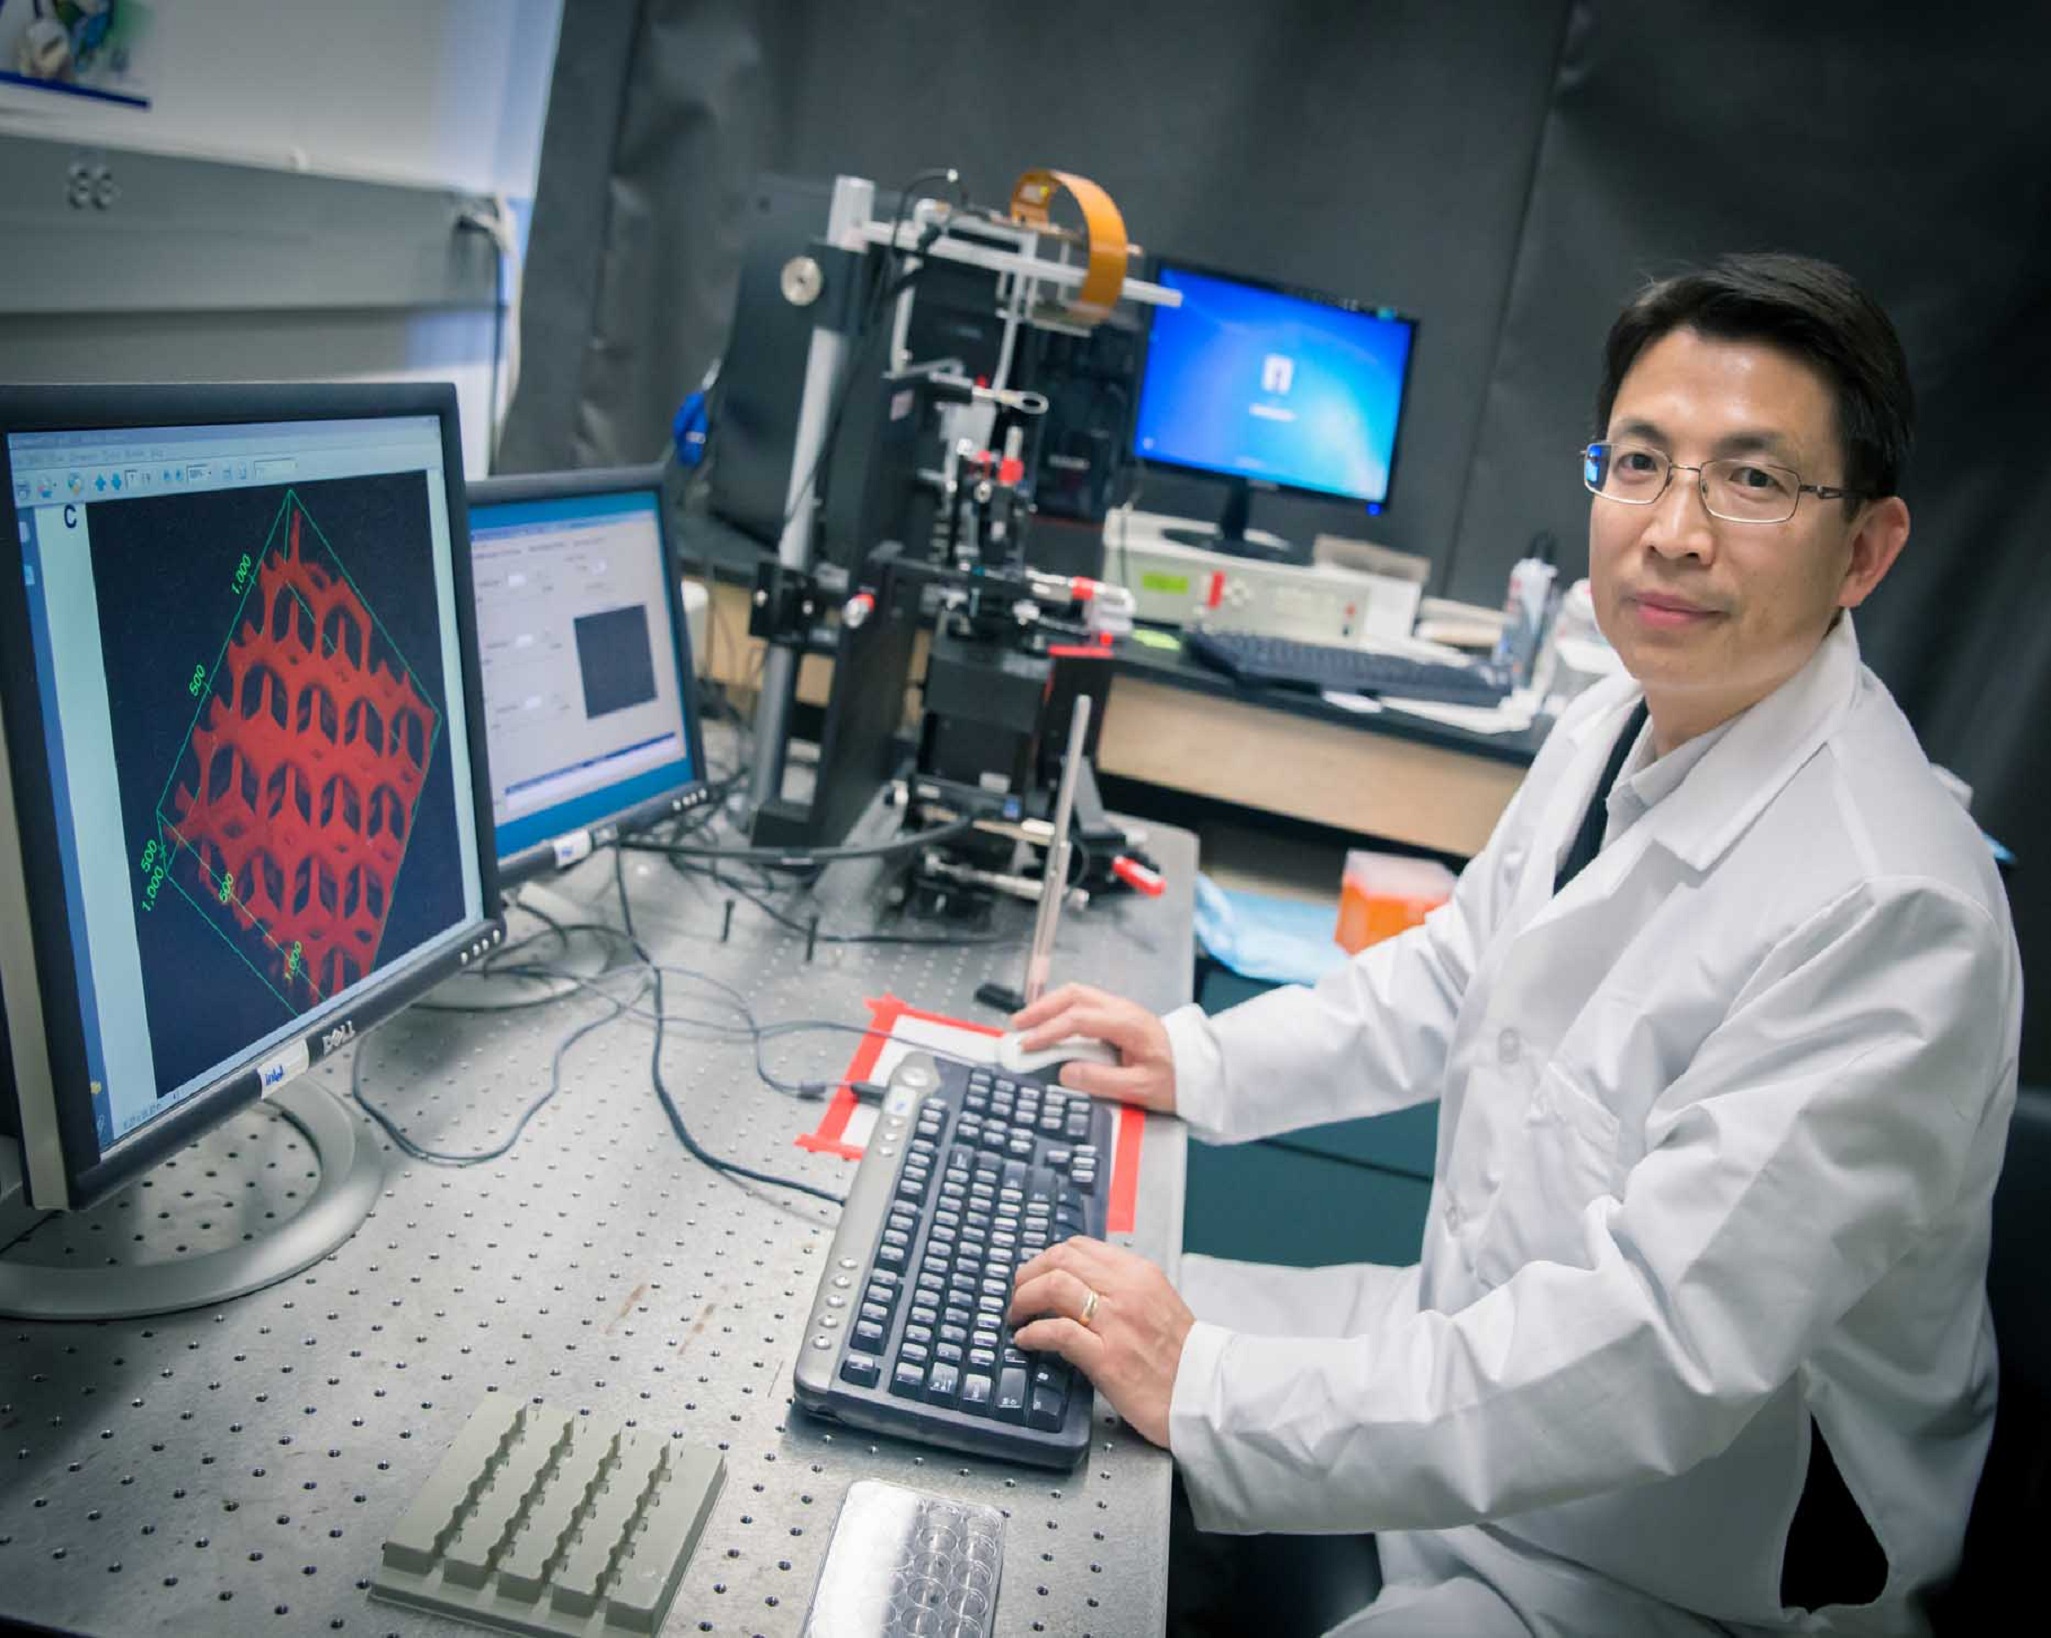

"Normalmente se tarda unos 12 años y se invierte 1,8 mil millones de dólares (casi 1,6 mil millones de euros) para fabricar un medicamento que cuente con el aprobado de la FDA", afirma Shaochen Chen, profesor de NanoIngeniería en la UCSD. Esa prolongación en el tiempo se debe a que más del 90 por ciento de los fármacos que se presenta no pasa las pruebas con animales o los ensayos clínicos humanos.

"Normalmente se tarda unos 12 años y se invierte 1,8 mil millones de dólares (casi 1,6 mil millones de euros) para fabricar un medicamento que cuente con el aprobado de la FDA", afirma Shaochen Chen, profesor de NanoIngeniería en la UCSD. Esa prolongación en el tiempo se debe a que más del 90 por ciento de los fármacos que se presenta no pasa las pruebas con animales o los ensayos clínicos humanos.

El modelo diseñado por la UCSD es lo que más se asemeja hasta ahora a una muestra de tejido de hígado humano, formado por una combinación diversa de células hepáticas (hepatocitos) y otras de apoyo organizadas sistemáticamente en un patrón hexagonal. "Se trata de un diseño funcional lo más similar a lo que se vería a través de un microscopio", puntualiza Chen.

Para ello, el equipo emplea una nueva técnica de bioimpresión desarrollada en su laboratorio, que permite producir rápidamente microestructuras complejas en 3D que imitan con máxima precisión las características de los tejidos biológicos. La impresión se realiza en dos fases. En primer lugar se imprime un patrón con forma de panal, con hexágonos de 900 micrómetros, introduciendo en cada uno células hepáticas derivadas de células madre pluripotentes inducidas, normalmente abreviadas como IPS (por las siglas en inglés de Induced Pluripotent Stem), células procedentes de cualquier parte del cuerpo que son capaces de “reprogramarse” como células madre.

El modelo diseñado por la UCSD es lo que más se asemeja hasta ahora a una muestra de tejido de hígado humano, formado por una combinación diversa de células hepáticas (hepatocitos) y otras de apoyo organizadas sistemáticamente en un patrón hexagonal. "Se trata de un diseño funcional lo más similar a lo que se vería a través de un microscopio", puntualiza Chen.

Para ello, el equipo emplea una nueva técnica de bioimpresión desarrollada en su laboratorio, que permite producir rápidamente microestructuras complejas en 3D que imitan con máxima precisión las características de los tejidos biológicos. La impresión se realiza en dos fases. En primer lugar se imprime un patrón con forma de panal, con hexágonos de 900 micrómetros, introduciendo en cada uno células hepáticas derivadas de células madre pluripotentes inducidas, normalmente abreviadas como IPS (por las siglas en inglés de Induced Pluripotent Stem), células procedentes de cualquier parte del cuerpo que son capaces de “reprogramarse” como células madre.